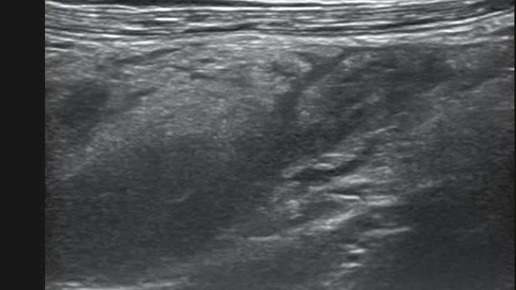

Ультразвуковые находки от врача УЗД Зорина Я.П.